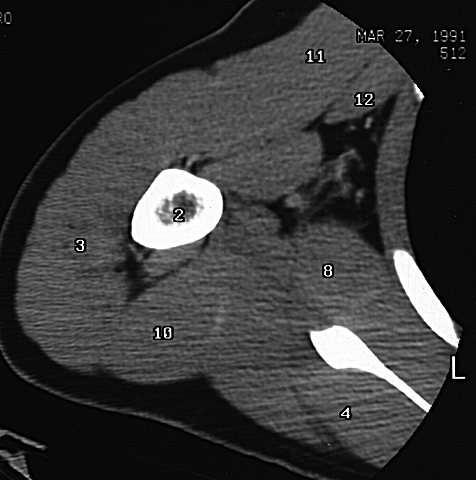

Radiology Images

Shoulder CT 4

2. Humerus

3. Deltoid m.

4. Infraspinatus m.

8. Subscapularis m.

10. Triceps m.

11. Pectoralis major m.

12. Pectoralis minor m.